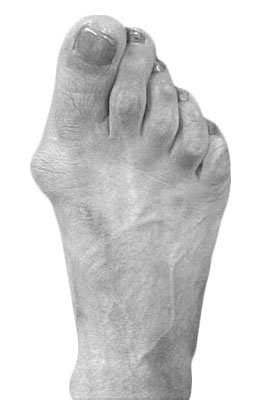

Minimally Invasive Bunion Surgery featuring the miniBunon™ System and Tailors Bunionectomy

Melissa is a 32-year-old businesswoman who could not be off her foot post-surgery, yet she had a severely painful bunion. We performed our miniBunon™ System (our trademarked minimally invasive bunion surgery) and had a dramatic correction with no downtime. Melissa continued to work after her bunion surgery and was back in shoes and full activity at 5 weeks. Melissa could not believe the results of her Bunionectomy resulting in no bony bump, no scar and amazing motion. “After” picture taken immediately following surgery. Note the bunion and bunionette (Tailor’s bunion) in the before picture.